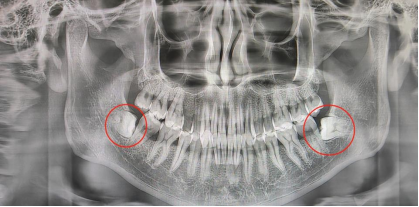

许多人可能会认为社区医院的医生水平不高,可锁金村社区医院口腔科经常会有其他医院不能拔的牙,跑到这里来处理,只因这里有一位在业界都受推崇的牙医戴荣烽。“别看智齿就一点点,如果用力不对,怎么拔也拔不出来,这很考验医生的技术。他在南京中大医院进修种植牙齿期间,遇到难拔的牙齿时,同行们有时也会请他相助”,中心主任助理高向丽说。

拔智齿不仅考验医生的耐心和细致程度,也是一项体力活,有的智齿甚至需要拔两三个小时。“横着或者倾斜生长的智齿通常很难拔除,怎么打磨以减少对相邻牙齿的影响,从什么方向用力,非常有讲究,如果用力不当,会影响到别的牙,把别的牙齿带松,甚至有时会把相邻的牙齿带出来”,戴医生对拔牙非常有心得,一位患者通过他的精细的操作,成功地将两颗横着生长智齿拔出,避免了对周围牙齿的影响。

“遇到智齿问题应尽早干预。一旦出现症状,应该立即拍摄牙齿全景片甚至口腔CT进行检查,如果不及时干预,慢慢地就会把前面牙齿的牙根顶坏,顶到牙齿报废,这个时候,不是拔一颗牙齿的问题,而是两颗牙齿都得拔”,戴医生建议道。